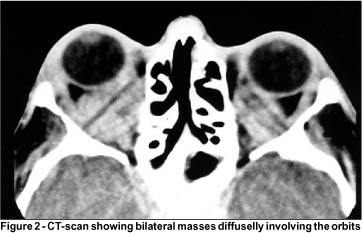

On examination, his best corrected visual acuity was 20/25 in the right eye (OD) and 20/20 in the left eye (OS). He had bilateral xanthelasmas in the superior and inferior eyelids and bilateral proptosis. Exophthalmometry (Hertel base 98) was 23 mm OD and 20 mm OS (Figure 1). The eyes were aligned in the primary position but there was marked restriction of elevation, adduction and abduction of both eyes. Slit lamp examination, pupillary reactions and intra-ocular pressure measurements were normal. Fundoscopy showed mild optic disc edema in OD. Computerized tomography (CT) of the orbits showed a hyperdense lesion diffusely involving the orbit (Figure 2). Magnetic resonance imaging disclosed diffuse infiltration of the orbits with a hypointense lesion in T1 (Figure 3) and T2 weighted images.

The differential diagnosis of Erdheim-Chester disease in the orbit is extensive and includes dysthyroid orbitopathy, idiopathic orbital inflammation, lymphoma, metastatic carcinoma and Langerhans' cell histiocytosis. None of these conditions is typically associated with xanthelasmas and they all should be ruled out based on clinical, laboratory and histopathological findings. Imaging is also very important as auxiliary method for early diagnosis of orbital Erdheim-Chester disease, although to date, no specific pattern of involvement has been defined. CT scan usually shows a diffuse infiltration of the orbit and eyelids (Figure 2). The same finding can be observed on MRI that reveals hypointense lesions on T1 and T2 weighted images. Ultrasonography shows a lesion with medium to high internal reflectivity(4). These imaging findings can lead to confusion with nonspecific inflammation of the orbit. However, in most cases of Erdheim-Chester disease involvement of the orbit is very extensive and there is characteristically absence of pain and inflammatory signs, which helps in the differentiation of this condition from nonspecific orbital inflammation.